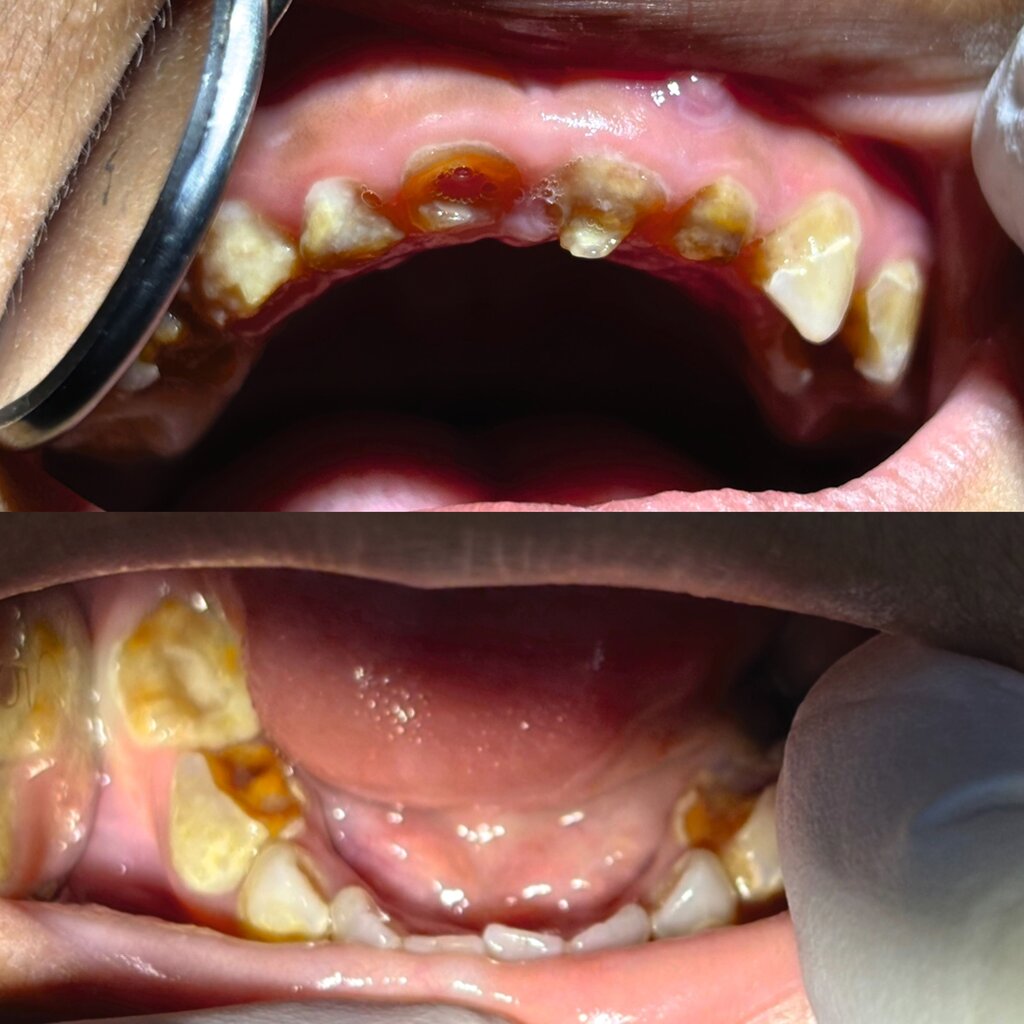

Herzzerreißend ist, dass dies bei Kindern noch stärker der Fall ist. Hier besteht ein großer Mangel an Aufklärung, Prophylaxe und Kontrollen. Die Kinder, die ich behandeln durfte, kamen alle aufgrund starker Zahnschmerzen. Ich hatte Füllungen erhofft, musste aber schnell feststellen, dass ich mich glücklich schätzen konnte, wenn es „nur“ eine Trepanation geworden war und nicht direkt eine Extraktion.

Oft entschied ich mich trotz verwirrter Blicke für eine Füllung, obwohl mir bereits die Zange gereicht worden war. „No, I will do a filling.“ musste ich mehrmals fest entschlossen erklären. „But it’s just a baby tooth!“ Und ich wurde angeguckt, als wäre ich verrückt. Das war eine Konversation, die ich am Anfang öfter hatte, doch meine Assistenz merkte schnell, dass Widerstand zwecklos war: Diese Milchzähne werden gerettet!

Natürlich habe ich auch Kinder gesehen, bei denen wir in Deutschland längst von Kindesmisshandlung sprechen würden. Sie hatten keinen einzigen Zahn, der nicht von Karies oder massivem Zahnstein befallen war.

Einen Patienten werde ich niemals vergessen: Er war nur fünf Jahre alt und hatte bereits an drei seiner Zähne Abszesse, die meisten Milchzähne waren durch Karies schon bis auf das Zahnfleischniveau zerstört. Der Mann, der ihn begleitet hatte, war offenbar nicht sein Vater und kannte das Kind nur oberflächlich. Mit ihm über die Ernsthaftigkeit des Falles und die Bedeutung von Mundhygiene zu sprechen, war leider nicht zielführend.